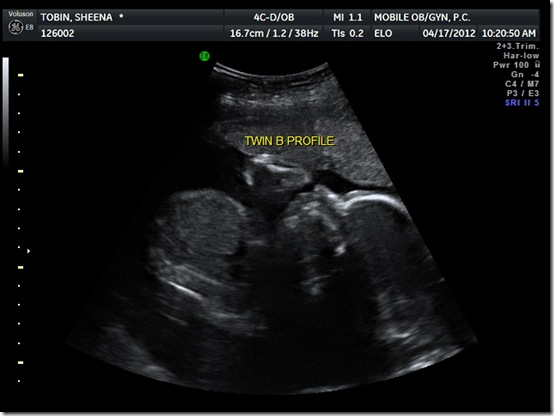

Now for the grand finale: the twins latest photo shoot. We had an ultrasound this morning showing our little morning glories in all their cuteness. Finally, they let us get a glimpse of their profiles:

They weigh a pound and half each and are both head down at the moment…in which position they’ll hopefully stay until d-day. Towards the end of the scan they were kicking each other and I was hoping and praying it was playful…so funny to watch. We also made sure to have the tech do a discount double check on the feminine anatomy just to make sure we weren’t in for any surprises at birth and once again, there’s no mistaking we’ve got two little princesses in there. :)

I’ll leave y’all with one last picture. Twin B was very interested in having her pictures taken today and, scary though it kind-of looks, she made sure to look right at the camera, although whether or not she was mouthing “cheese” is debatable: